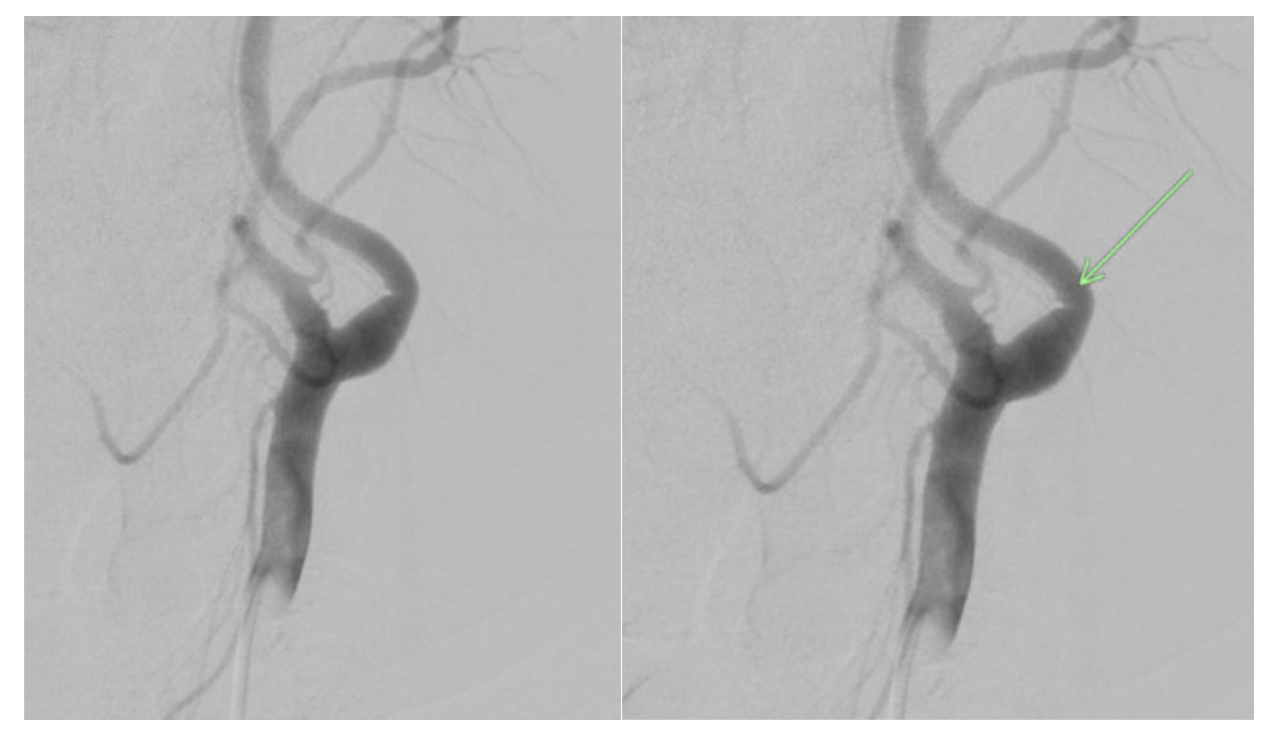

Given the small size of the carotid web, no intervention was performed. The patient was discharged home on the same medication regimen. A complete rheumatologic and hematology panel ruled out secondary causes of coagulopathy possibly causing recurrent thrombi. After 12 months, the patient presented following 10 minutes of left arm numbness and facial drooping with complete recovery at the time of presentation. MRI showed small acute cortical infarcts involving the left precentral gyrus and parietal lobe. Again, a complete workup was negative. This time, the patient was discharged adding 75 mg of clopidogrel to her regimen, but 4 months later she was readmitted with the same symptoms of 1-hour duration. She was given tPA, now a third time, and MRI showed acute stroke of the left medial cerebral artery territory. Again, workup failed to show a source of the recurrent strokes. Given the failure of dual antiplatelet therapy, clopidogrel was stopped and 5 mg of apixaban twice daily was added. After this medication adjustment, the patient has been stroke-free for 5 years, with consistent follow-up in clinic.

Recurrence of cardiovascular accidents (CVA) occurs frequently. Studies have demonstrated recurrence of CVA in 26% of patients within 5 years.3 This case reports a patient on antiplatelet therapy with recurrent CVA with no identifiable cause. Her stroke was classified as cryptogenic due to a lack of evidence of etiology despite repeated tests to rule out cardioembolic, aortoembolic, or atheroembolic causes. Since all the strokes occurred within the region of the left internal carotid artery (Figures 2-4), we suspect they were caused by the left internal carotid web. During DSA, the neurosurgeon noted in the operative note that the extracranial left carotid artery circulation exhibited normal caliber and course, with the exception of a very small, eccentric intimal web at the junction of the left internal carotid artery bulb and proximal cervical segment. While most carotid webs are found in the carotid bulb’s posterior margin, the carotid web in this case appeared in the anterior and distal aspect. Theoretically, a carotid web could form anywhere along the carotid artery where a thin, membrane-like shelf of tissue that extends from the wall to the lumen exists. The multitude of infarcts in the left internal carotid’s territory helps to support that this patient has a carotid web rather than a kinked or tortuous vessel, and that it has a probable role in stroke etiology.